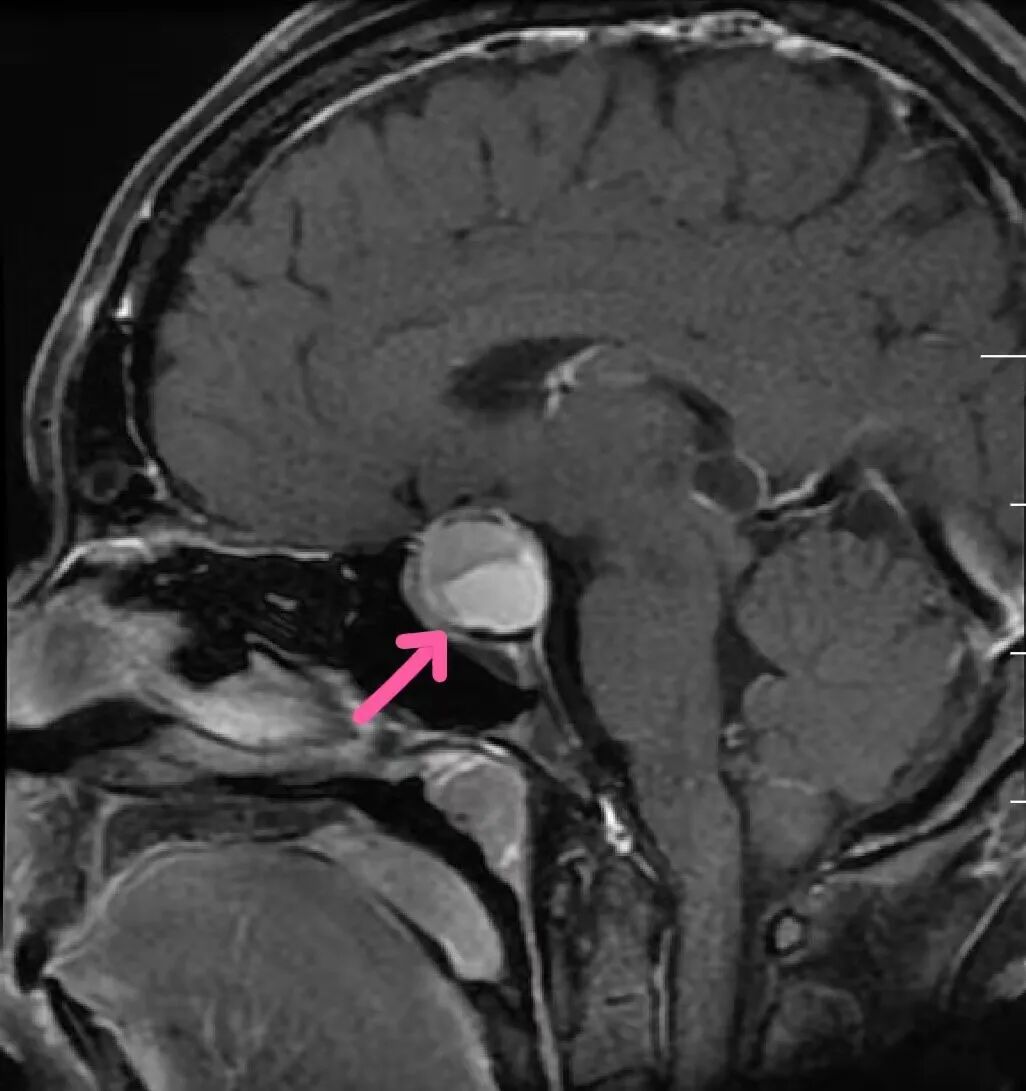

(小美的颅咽管瘤)

这个肿瘤正是颅咽管瘤,正常人颅脑底部存在两个重要结构——人体活动的调节中枢下丘脑和分泌各种激素的垂体,而颅咽管瘤就主要长在下丘脑-垂体区域,虽然这个肿瘤为良性,但我们的“脑袋”寸土寸金,在有限的空间里,原住民们紧挨着有序开展各项生产工作,根本就没有多余的空间给颅咽管瘤生存,它的出现必定是要侵犯其他“原住民”,小美的颅咽管瘤有2.3厘米大,压迫到了垂体,垂体是身体内最复杂最重要的内分泌腺,垂体一旦被侵犯压迫,小美的各项激素就可能混乱,这就是小美长年月经不规则的原因,激素水平不正常更无法正常生育。